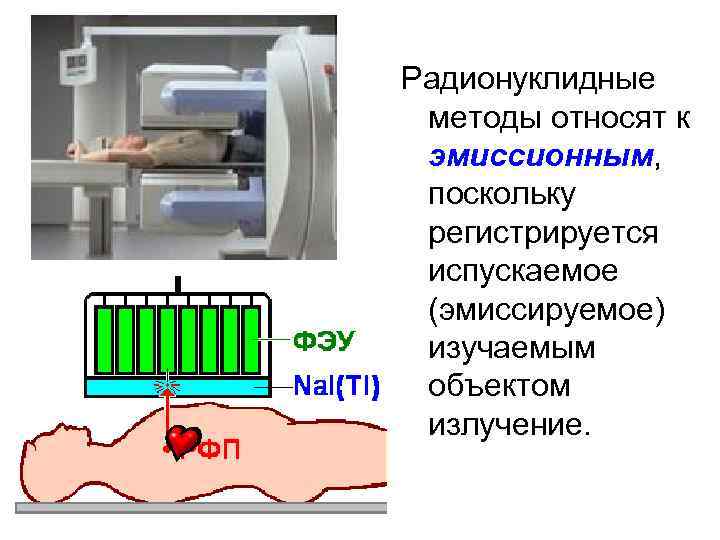

Радионуклидные методы относят к эмиссионным, поскольку регистрируется испускаемое (эмиссируемое) изучаемым объектом излучение.

Радионуклидные методы относят к эмиссионным, поскольку регистрируется испускаемое (эмиссируемое) изучаемым объектом излучение.